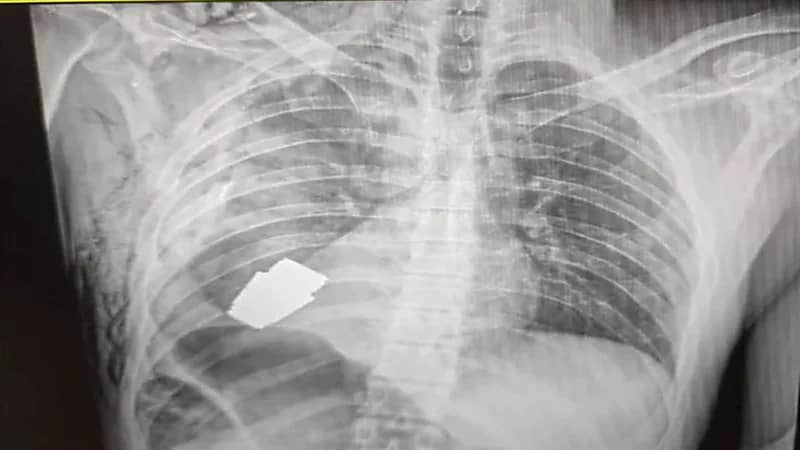

نجح جرّاح عسكري في إزالة قنبلة حية استقرت داخل جسد جندي أوكراني وعرضت حياته للخطر إذ إنها يمكن أن تنفجر في أية لحظة.

وقال حاكم منطقة باخموت الأوكرانية، سيرهي بورزوف، إن الأطباء العسكريين أجروا عملية جراحية لإزالة القنبلة غير المنفجرة من جسد الجندي.

وأشار إلى أن الطبيب أجرى العملية و اضطر خلالها لعدم استخدام إجراء التخثير الكهربي الذي يعتمد على الحرارة للتحكم في النزيف وتدمير الأنسجة غير الطبيعية، مبيناً أن استخدام هذا الإجراء من الممكن أن يؤدي إلى انفجار القنبلة.

وأبان أن إزالة القنبلة اليدوية تمت بنجاح، وجرى إرسال الجندي المصاب لإعادة التأهيل والتعافي.